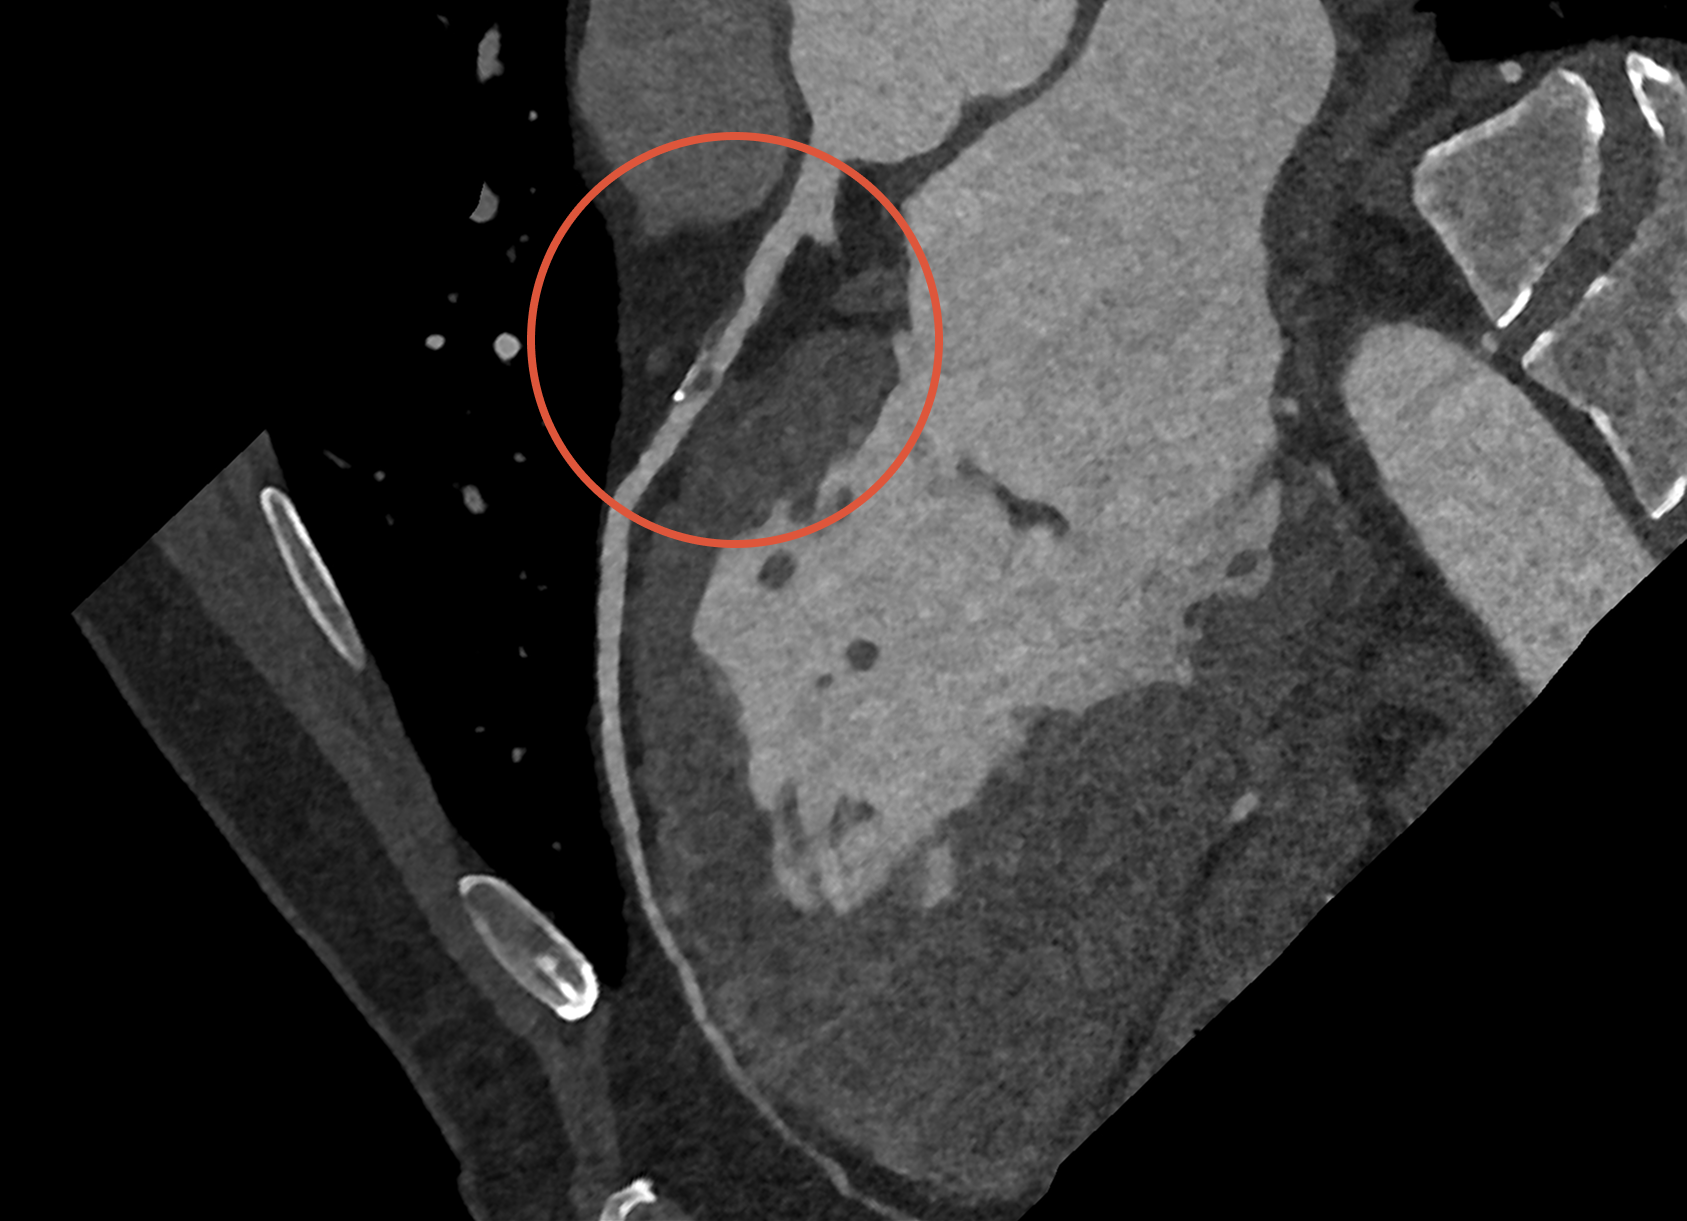

Placken kan bestå av mjukare plack eller förkalkade plack. Mjukare plack innehåller fett och kolesterol, men syns inte på en Calcium score undersökning. Förkalkade plack innehåller kalcium, vilket gör dem hårdare och synliga vid både DT-Hjärta och Calcium score.

När placken växer kan de tränga in i kärlets lumen (den öppna kanalen där blodet flödar) och orsaka förträngningar. Detta kan försämra blodflödet till hjärtat, vilket i värsta fall leder till kärlkramp eller hjärtinfarkt. Det mest riskfyllda är dock att ett plack kan brista. Då kan en blodpropp snabbt bildas och helt blockera blodflödet i kranskärlet – det är ofta detta som orsakar en akut hjärtinfarkt.

Hjärtscanning kan påvisa huruvida du har ateroskleros (åderförfettning eller åderförkalkning). Det finns två olika metoder. Den enklaste varianten mäter förekomst av förkalkningar i kranskärlen, så kallat ”coronary artery calcium score”. Det finns ett starkt samband mellan calcium score, mängden ateroskleros och framtida risk för hjärtkärlsjukdom. 5-10% med ateroskleros har plack utan förkalkning och dessa syns inte vid användande av calcium score. Dessa plack är i regel farligare än de med förkalkning i sig. För att även kunna se dessa förändringar behöver man göra en datortomografi av kranskärl där man tillför kontrastmedel vilket är den andra metoden - Datortomografi av hjärtat.